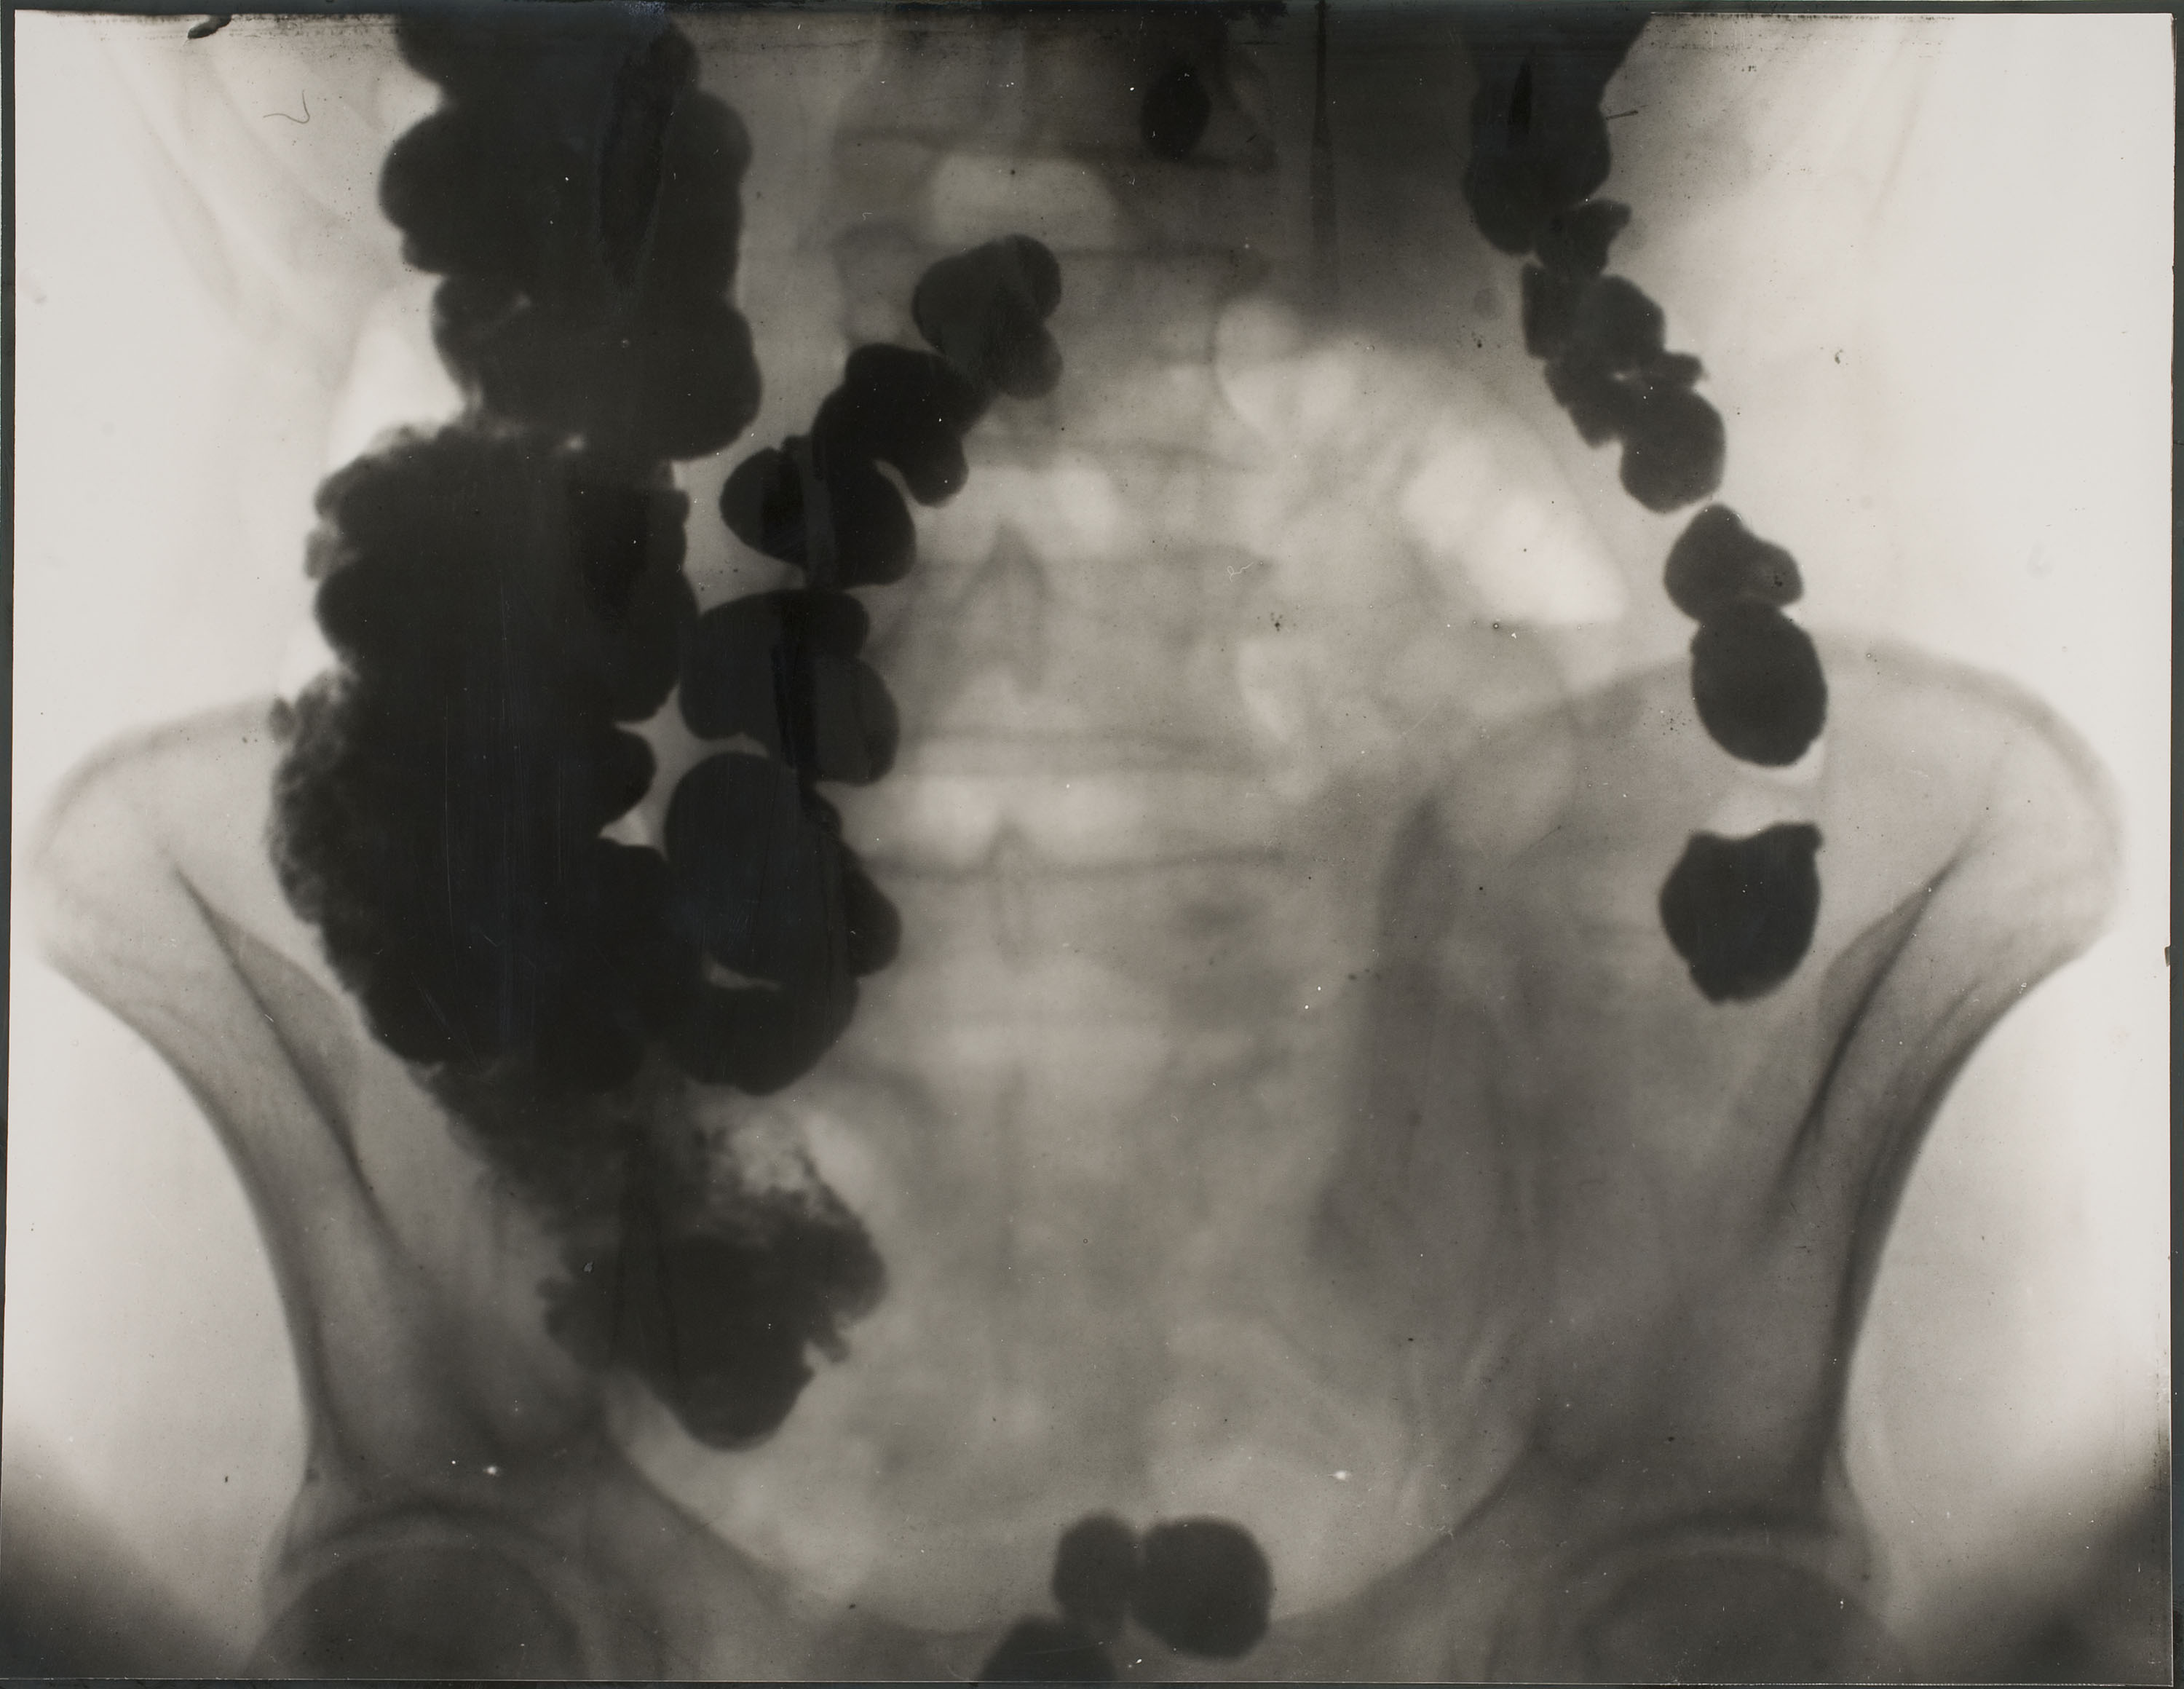

X-ray

Photography

1928

i.s. 36 x 27.5 cm

Gelatin and silver on paper